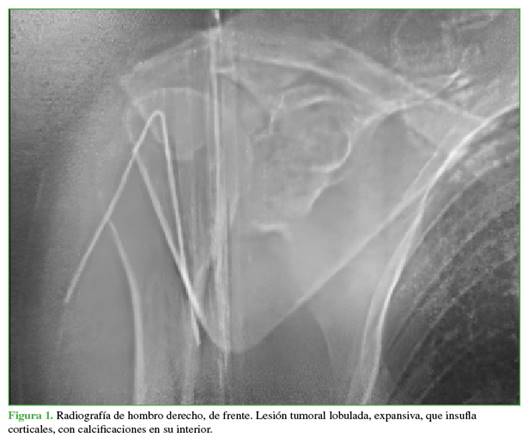

Hombre de 47 años, que consultó por omalgia derecha de un año de evolución. En el examen físico, se detectó dolor e impotencia funcional, con limitación de todos los rangos de movilidad del hombro. Se solicitaron radiografías, una tomografía computarizada (TC) y una resonancia magnética de hombro. Se visualizó una lesión tumoral lobulada, expansiva, que insuflaba corticales, con calcificaciones en su interior (Figura 1). En los cortes sagitales de la TC, se apreciaron imágenes hipodensas en el interior de la glena y, en la resonancia magnética en secuencia en T2, se observó hiperintensidad en la fosa supraespinosa que comprometía los músculos infraespinoso y subescapular (Figura 2).

El condrosarcoma representa el 20-25% de los sarcomas, es la segunda neoplasia maligna más frecuente después del osteosarcoma. Se localiza principalmente en la pelvis y las regiones de los huesos largos, como el fémur y el húmero, y con menos frecuencia, en la escápula.6 El subtipo convencional es la variante más común (80-90%). La edad típica de presentación es la cuarta y quinta década de la vida. Los síntomas y signos que provoca el condrosarcoma de escápula pueden incluir dolor en el área afectada, un bulto o hinchazón visible, limitación del movimiento del hombro. A medida que la enfermedad avanza, el dolor puede intensificarse y pueden aparecer otros cuadros, como debilidad o problemas neurológicos si el tumor presiona estructuras cercanas. Se diagnostica principalmente con radiografías y TC, que muestran características, como destrucción expansiva y osteolítica, masas de tejidos blandos y calcificaciones. La biopsia por punción guiada por TC es esencial para un diagnóstico preciso.7